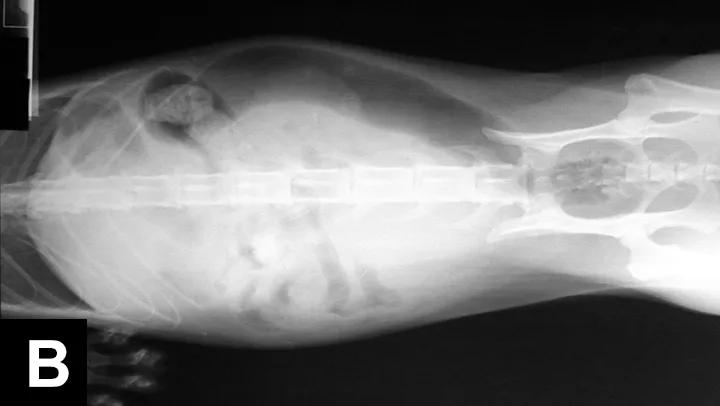

Tests for FIV and FeLV were negative. CBC revealed a mild monocytosis and neutrophilia. A serum chemistry panel revealed azotemia and mild hyperglycemia (Table 1). Urinalysis via cystocentesis revealed concentrated urine with RBCs too numerous to count and mucus strands. The remainder of the urinalysis was within normal limits. No bacteria were seen. Urine culture was negative. Survey radiographs revealed a gas pattern in the GI tract, an enlarged bladder, and ileus throughout the small bowel (Figure 1). No stones were visible in the kidneys, ureters, bladder, or urethra.

Figure 1

Lateral (A) and ventrodorsal (B) radiographs showed a distended urinary bladder, ileus, and a GI obstructive pattern with possible gastric and small bowel foreign bodies.